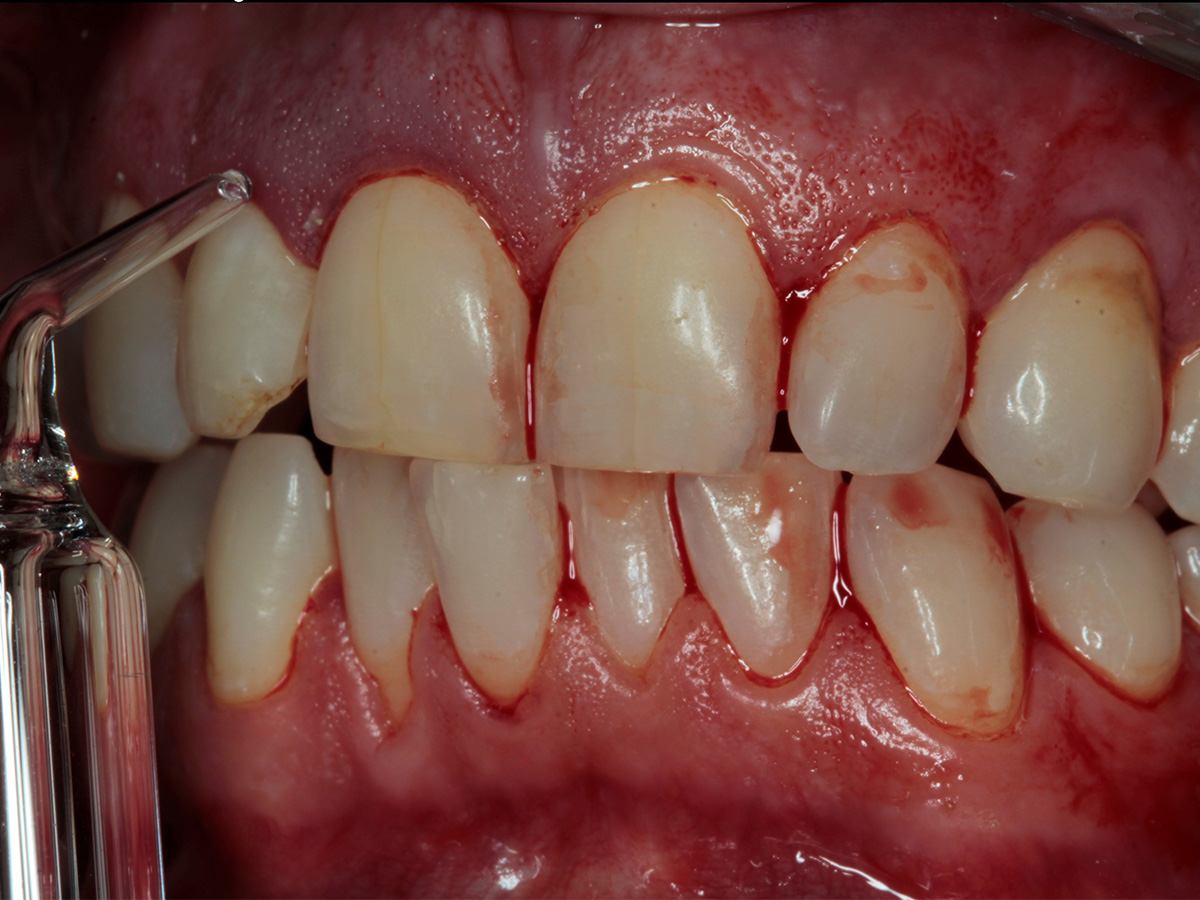

KURSINHALT

In diesem Workshop erhalten Sie umfassendes Wissen für die Behandlung von Parodontitis-Patientenen. Zunächst führt Sie Yvonne Gebhardt durch moderne subgingivale Behandlungskonzepte – das Herzstück der PA-Therapie. Anschließend erklärt Ihnen Sonja Steinert die faszinierenden Zusammenhänge des Knochenstoffwechsels: Wie Entzündungen den Knochenabbau fördern und wie Sie mit gezielter Therapie und Vitamin D gegensteuern können.

• Parodontale Krankheitsbilder erkennen